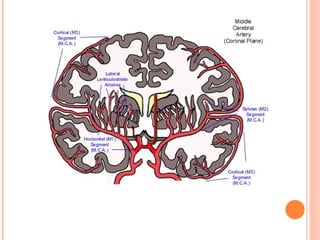

MIDDLE CEREBRAL

ARTERY

 Larger, more direct continuation of ICA

 Occupies lateral sulcus

 Central branches →Head of caudate

nucleus,Putamen, Lateral pallidum, Internal

capsule [anterior limb, genu, posterior limb],

External capsule, Claustrum, Lateral

hypothalamus

 Larger, moredirect continuation of ICA  Occupies lateral sulcus  Central branches →Head of caudate nucleus,Putamen, Lateral pallidum, Internal capsule [anterior limb, genu, posterior limb], External capsule, Claustrum, Lateral hypothalamus